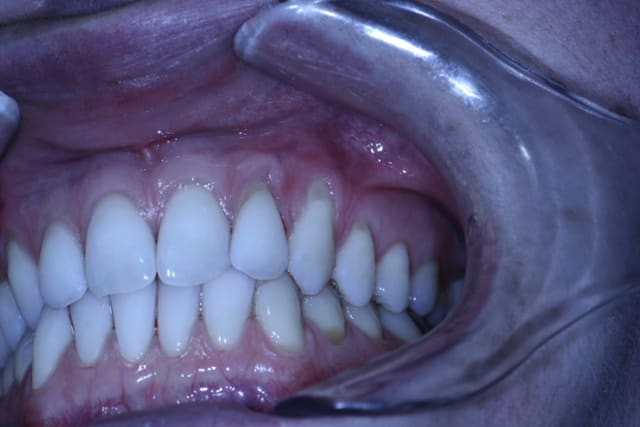

J'hésite sur le choix de la technique.

La patiente est jeune, non fumeuse, aucun problème de santé et très préoccupée par son problème de gencive.

En clair très motivée.

Les récessions sont des Cl I de Miller, donc bon pronostic.

Je penchais pour un conjonctif sur 23 et un lambeau semi-lunaire positionné coronairement sur la 22.

Mais dans une même séance ça paraît difficile.